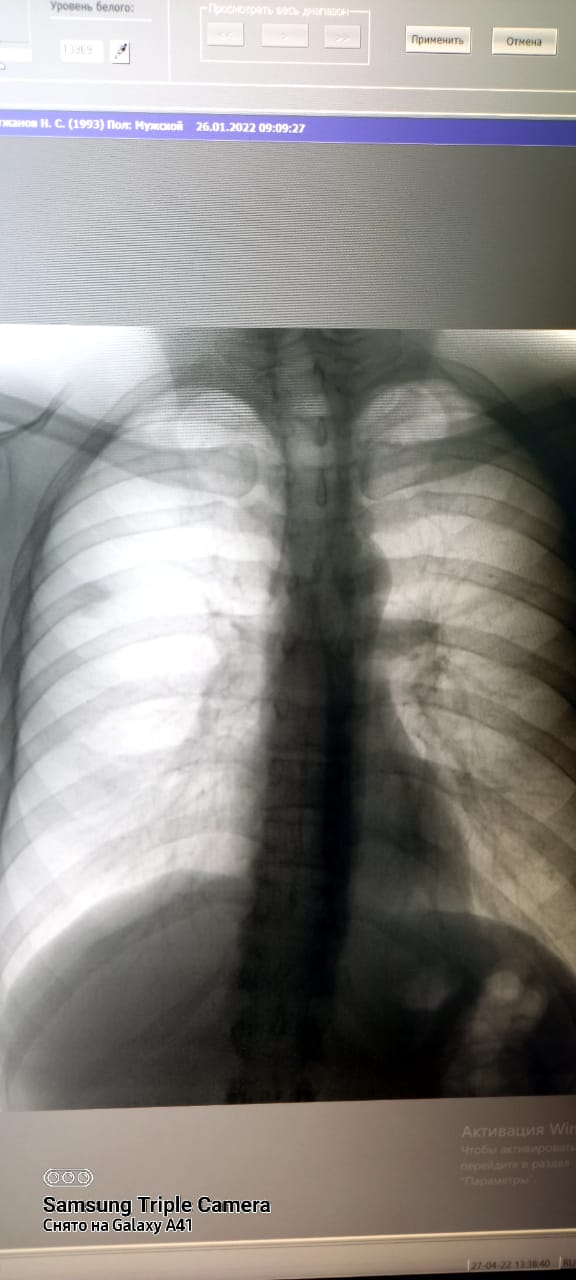

Туберкулез-инфекционное заболевание, возбудитель которого является Мycobacterium tuberculosis. Основной путь передачи туберкулезной инфекции-воздушно-капельный. Основным источником распространения инфекции являются больные туберкулезом легких. Передача заболевания происходит при вдыхании человеком зараженного микобактериями воздуха. Обычно заражение происходит в посещениях. Проветривание и хорошая вентиляция удаляют капельку из воздуха помещения, а прямые солнечные лучи быстро убивают микобактерии туберкулеза. Туберкулез излечим. Для выявления туберкулеза и других заболеваний используется в городской поликлинике №5 имеется новый флюорографический аппарат "ПРОСКАН-2000". Исследования проводятся с 15-летного возроста и старше, и по показаниям флюорография проводится 2 раза в год.